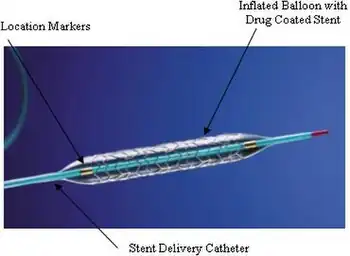

Drug-eluting stent

Drug-eluting stents (DES) are specialized medical devices used to treat coronary artery disease and peripheral artery disease. They release a drug that inhibits cellular growth into the blocked or narrowed arteries, reducing the risk of blockages. DES are commonly placed using percutaneous coronary intervention (PCI), a minimally invasive procedure performed via catheter. These stents have shown clear advantages over older bare-metal stents, improving patient outcomes and quality of life for cardiac patients. With over 90% of stents used in PCI procedures being drug-eluting as of 2023, DES have become the standard choice for interventional cardiologists.

DES gradually release drugs that prevent restenosis and thrombosis within the treated arteries, addressing common complications associated with previous treatments. While risks such as clot formation and bleeding exist, studies have demonstrated superior efficacy compared to bare-metal stents in reducing major adverse cardiac events like heart attacks and repeat revascularization procedures. Long-term outcomes are still being studied due to their relatively recent introduction; however, DES have revolutionized the treatment of coronary artery disease by significantly improving patient outcomes and enhancing their quality of life.